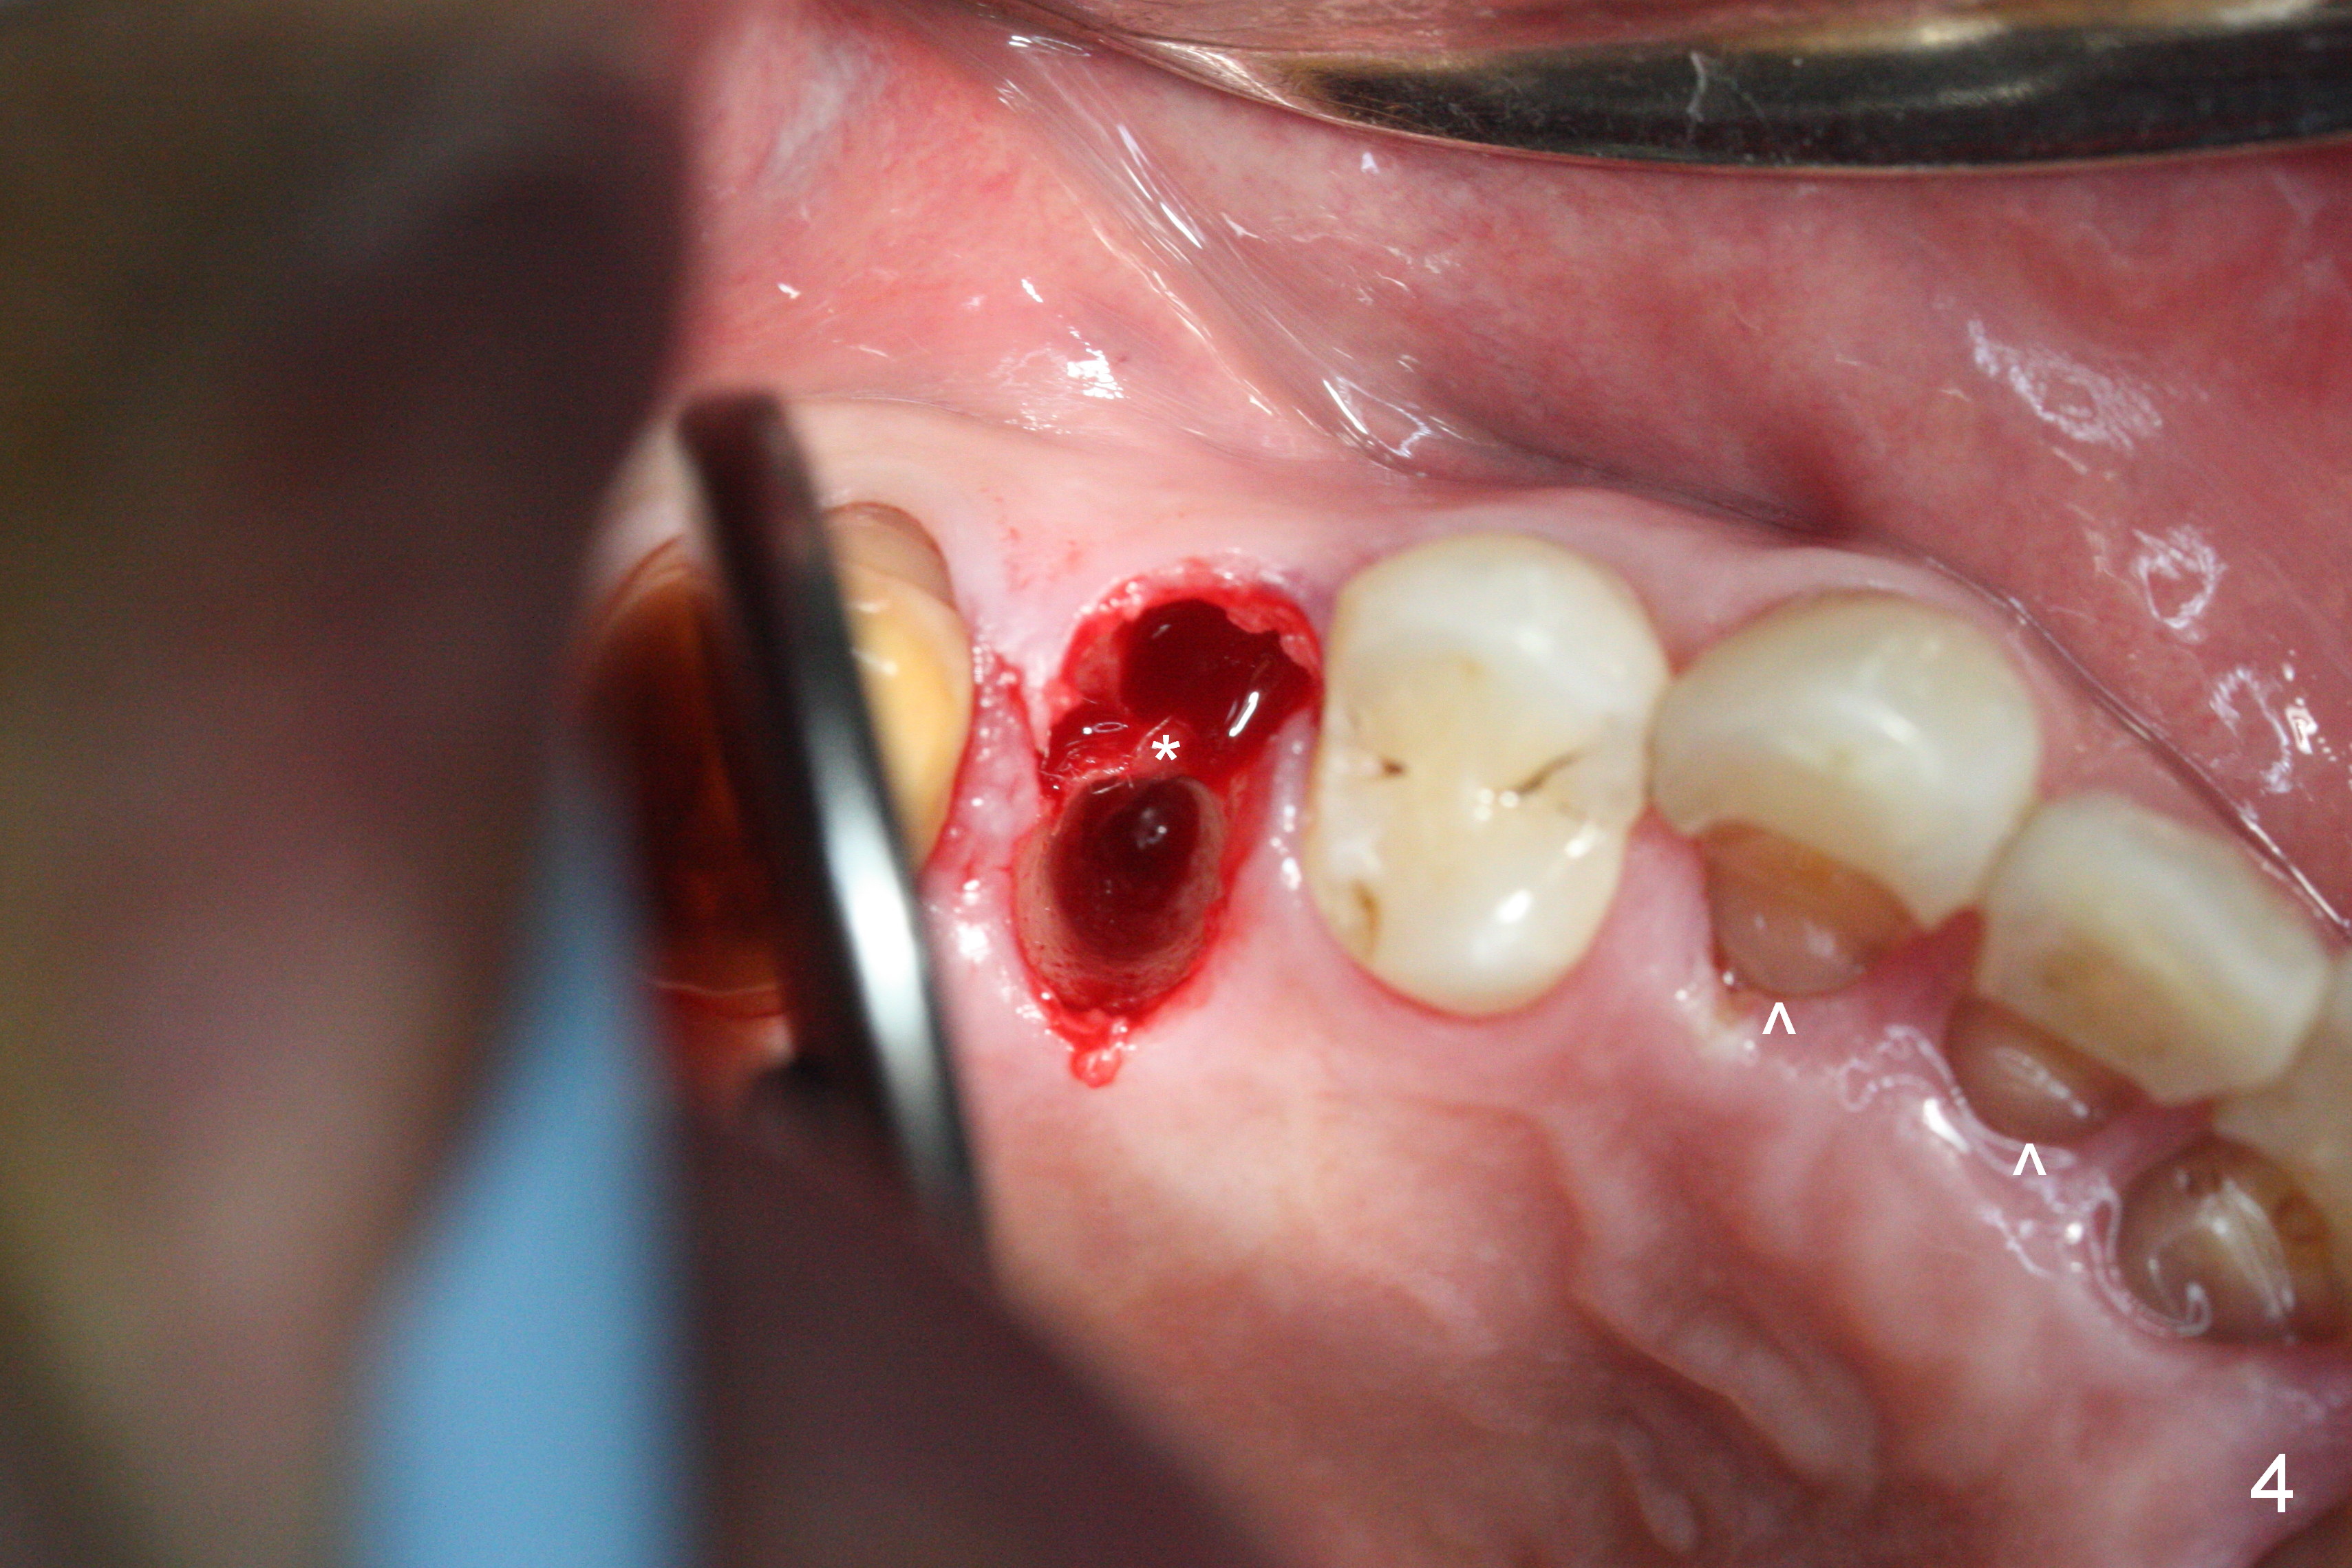

Preop exam shows posterior occlusal collapse (Fig.1) with #3 lost crown and #4 residual root. There is no ridge atrophy at #2 buccopalatally (Fig.2). The root stump of the tooth #4 is oblong, apparently consisting of 2 roots (Fig.3). There is a pointed septum at #4 socket (Fig.4, severe palatal wear of the anterior teeth (^)). After the septum is flattened with surgical handpiece and #8 round bur, 1.6 mm drill is used to start osteotomy in the septum, followed by Magic Drills (MD) and Magic Expanders (ME) alternatively. Osteotomy at #2 is initiated with Magic split, followed by MD and ME in the same manner. Dummy implants are tried in (Fig.5). Because of limited vertical height, Magicore (5.5x9(1) mm) is placed at #2, while a 4x13 mm FC implant 1-2 mm deeper than usual at #4 (Fig.6, ~ 55 Ncm). When a 5x4(2) mm pair abutment is placed at #4, there is no clearance between the Magicore at #2 and the abutment and the opposing dentition. A splinted provisional is fabricated at #3 and 4 to increase the posterior vertical height (Fig.7 P,8). In fact the occlusal contact is confined to the portion of the provisional at #3. The provisional has to extend to #4 to keep bone graft (Fig.6 *) and collagen plug in place. Liquid food is recommended at least 2-3 weeks, since there is no functional occlusal contact on the left. When the wound heals at #4 approximately 2-3 weeks, the splinted provisional can be sectioned with removal the portion at #4 to reduce micro-movement. By the evening the patient is doing well without nasal hemorrhage (sinus lift at #2 (Fig.6 *) or TMJ disturbance (due to increased vertical height).